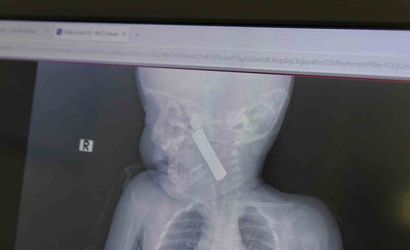

Karaman Eğitim ve Araştırma Hastanesi acil servisine kusma şikayetiyle getirilen 6 aylık E.A. isimli kız bebeğin yapılan muayene ve tetkiklerinde boğazına kumanda pili kaçtığı tespit edildi. Solunum güçlüğü yaşayan bebek, çocuk cerrahisi ekibi tarafından acilen ameliyata alındı.

Yapılan tetkiklerde pilin ağız tabanına oturduğu ve yemek borusunun birinci darlığına kadar uzandığı görüldü. İlk muayenede bebekte belirgin siyanoz ve solunum sıkıntısı vardı; oksijen satürasyonunun yaklaşık 90 civarında olduğu bildirildi. Durum acil olduğundan, ekip vakit kaybetmeden ameliyathaneye yöneldi.